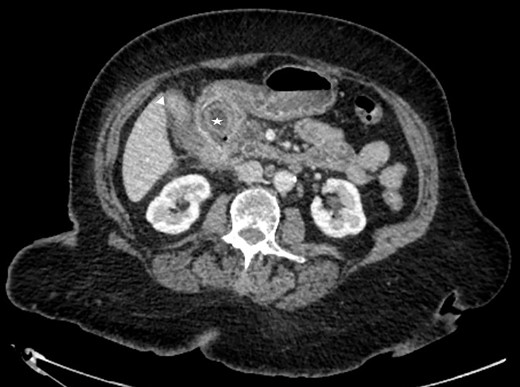

A frail 83-year-old female attended the emergency department with epigastric pain, vomiting and signs of sepsis with a heart rate of 101 and a temperature of 38°C. She had a recent admission with severe cholecystitis that was managed conservatively with intravenous antibiotics. On examination, she had tenderness in the right upper quadrant. Blood revealed an acute kidney injury, a CRP of 189 with normal liver function tests. Axial imaging demonstrated aerobilia with a dilated common bile duct of 14 mm and there was a 3.5 cm stone impacted in the first part of duodenum with evidence of a cholecysto-duodenal fistula (Figs 1–3).

CT scan showing the stone impacted in the first part of duodenum.